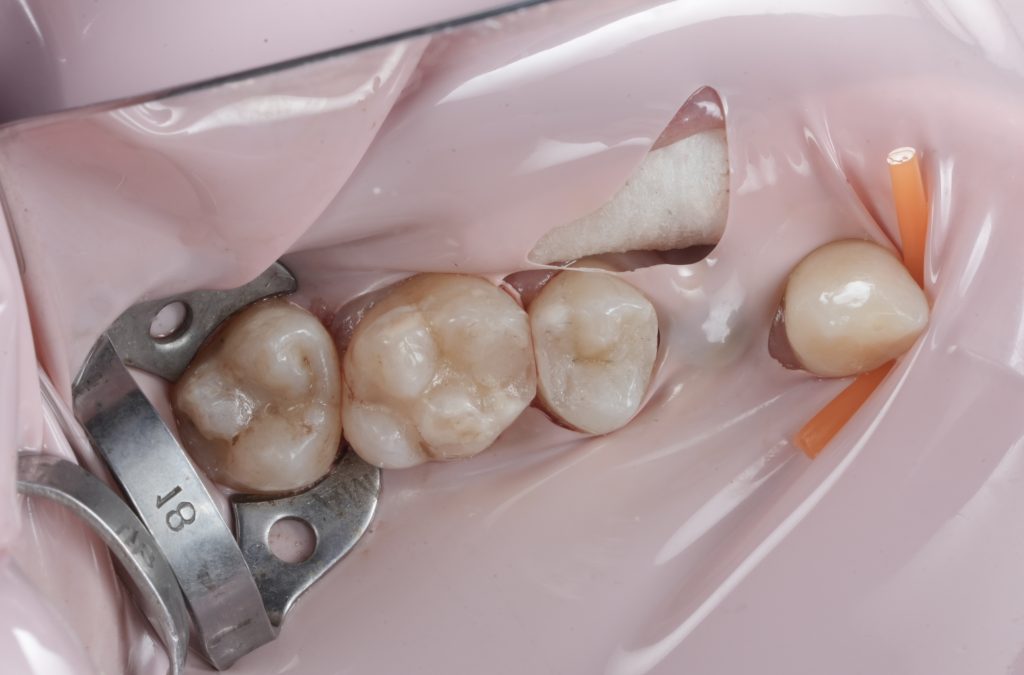

- Fig. 3: Rubber dam isolation (wide view).

- Fig. 4: Pre-wedge / separation setup (before prep).

Images to place

- Fig. 7: Sectional matrix + wedge placed.

- Fig. 8: Ring in place (occlusal view showing band adaptation).